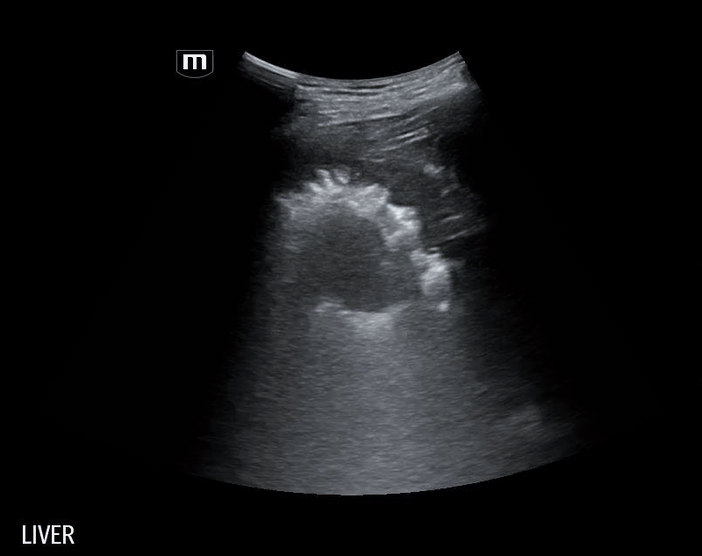

Using the curvilinear probe, we see a well-defined, round lesion within the liver parenchyma on the right lower quadrant US:

Based on the patient’s ultrasound findings, the appearance is consistent with a hepatic abscess.

Hepatic Abscess: Key Sonographic Features

• Appearance: focal, hypoechoic or complex cystic lesion within liver parenchyma

• Echotexture: heterogeneous, may contain septations, debris, or internal echoes

• Borders: irregular or ill-defined; chronic abscesses may develop capsule

• Gas formation: echogenic foci with dirty shadowing or ring-down artifacts (seen in Klebsiella/E. coli)

• Posterior acoustic enhancement: fluid-filled lesion characteristic

• Color Doppler: peripheral hyperemia, absent central vascularity

• Location: most commonly in the right hepatic lobe due to its greater blood supply and biliary drainage.

• Multiple hepatic abscesses, the largest located in the right hepatic lobe, measuring 13.3 cm